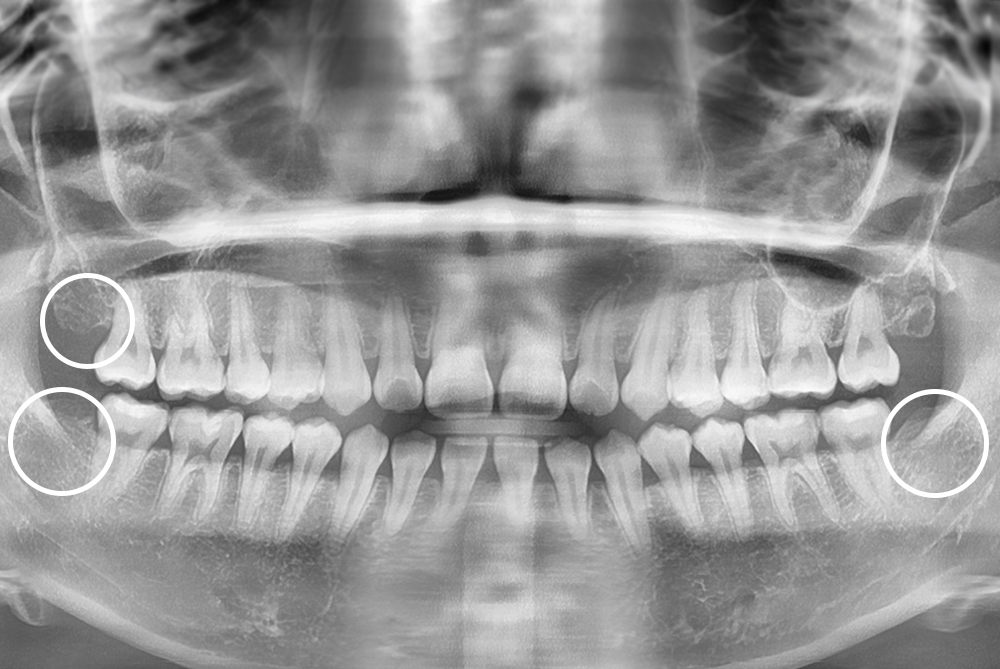

[사랑니] 매복 사랑니 발치

치료후 : 2019-08-26

세종치과는 구강악안면외과학 박사이신 원장님이 발치하는 치과입니다.